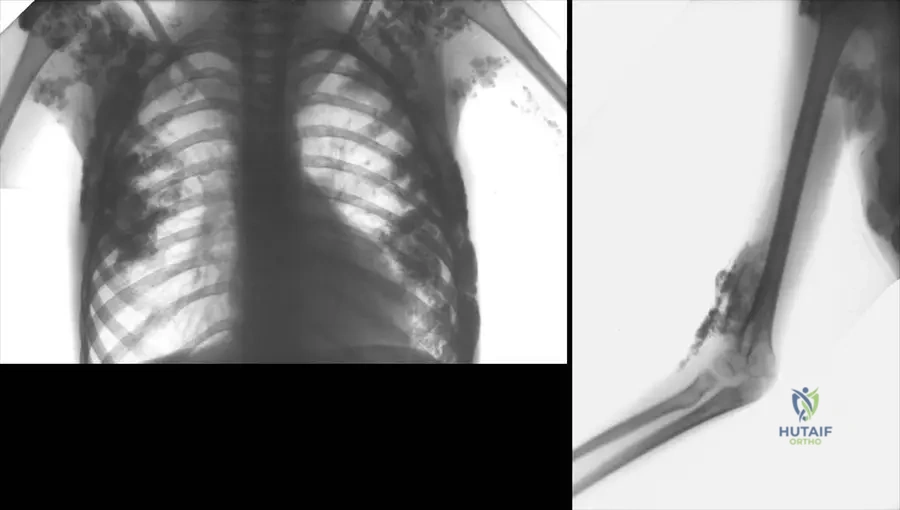

A 65-year-old male presents to the clinic with persistent pain and limited function of his right hip, 3 years after a total hip arthroplasty. On examination, there is erythema and induration in the right gluteal region, and he reports systemic symptoms including fever. The image shows local signs of inflammation with pus about to break through the skin.

Rationale: The clinical vignette and image describe classic signs of a periprosthetic joint infection (PJI): persistent pain, limited function, erythema, induration, pus formation, and systemic symptoms like fever. The image specifically shows local signs of inflammation with pus about to break through the skin, which is a hallmark of deep infection. Aseptic loosening (A) would typically present with pain but without the prominent inflammatory signs, pus, or systemic fever. Heterotopic ossification (B) is calcification in soft tissues and would not present with pus or systemic fever. Deep vein thrombosis (D) would present with swelling and pain, but typically not erythema, induration, or pus in the gluteal region, nor fever in this context. Sciatic nerve irritation (E) would present with neurological symptoms, not local inflammation and pus.